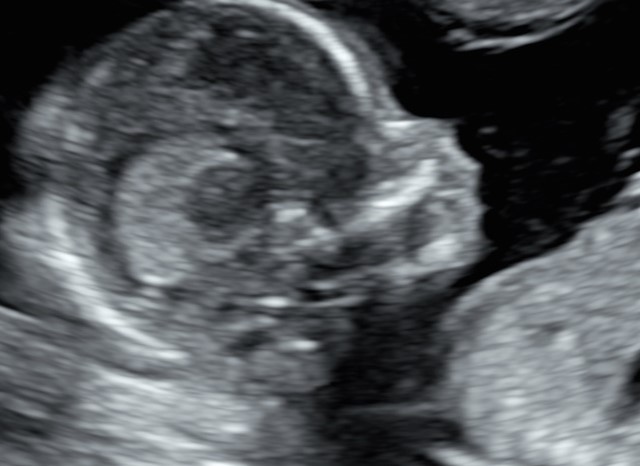

Siamo arrivati al quarto mese. Le incertezze, precauzione e scaramanzie dei mesi precedenti, stanno lasciando il passo a consapevolezza e gioia. L’espressione tipica dei genitori quando guardano il loro “tesoro” a queste settimane è “non pensavo che si vedessero così tante cose e che fosse già così bambino”. Infatti l’impressione ricevuta a queste settimane è di un tesorino alto 14-16 cm e del peso di poco più di 100-180 g, con tutte le sue cosine a loro giusto posto.

A questa epoca è possibile condurre un esame che impropriamente viene definito pre-morfologico, che ci permette di valutare le strutture principali, il tanto da poter affrontare con tranquillità il fondamentale appuntamento con l’ecografia morfologica del V mese.